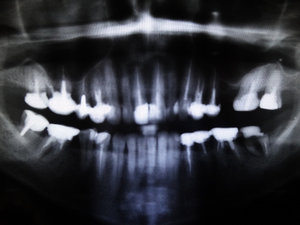

Я живу в маленьком поселке. И то, что предлагают местные врачи, меня не совсем устраивает. Хотелось бы услышать мнение стороннего специалиста. Помогите определиться с планом протезирования?

Комментарий №176991

• Исключительно по ортопантомограмме составить план лечения невозможно. Требуется клинический осмотр и оценка прикуса. Но, совершенно однозначно, перед протезированием требуется терапевтическая реабилитация. Зубы 17-й, 16-й, 15-й, 14-й, 24-й, 25-й, 26-й, 36-й, 35-й, 46-й, 47-й оценить состояние на прицельном рентгеновском снимке. Вероятнее всего потребуется перелечивание корнев читать далее